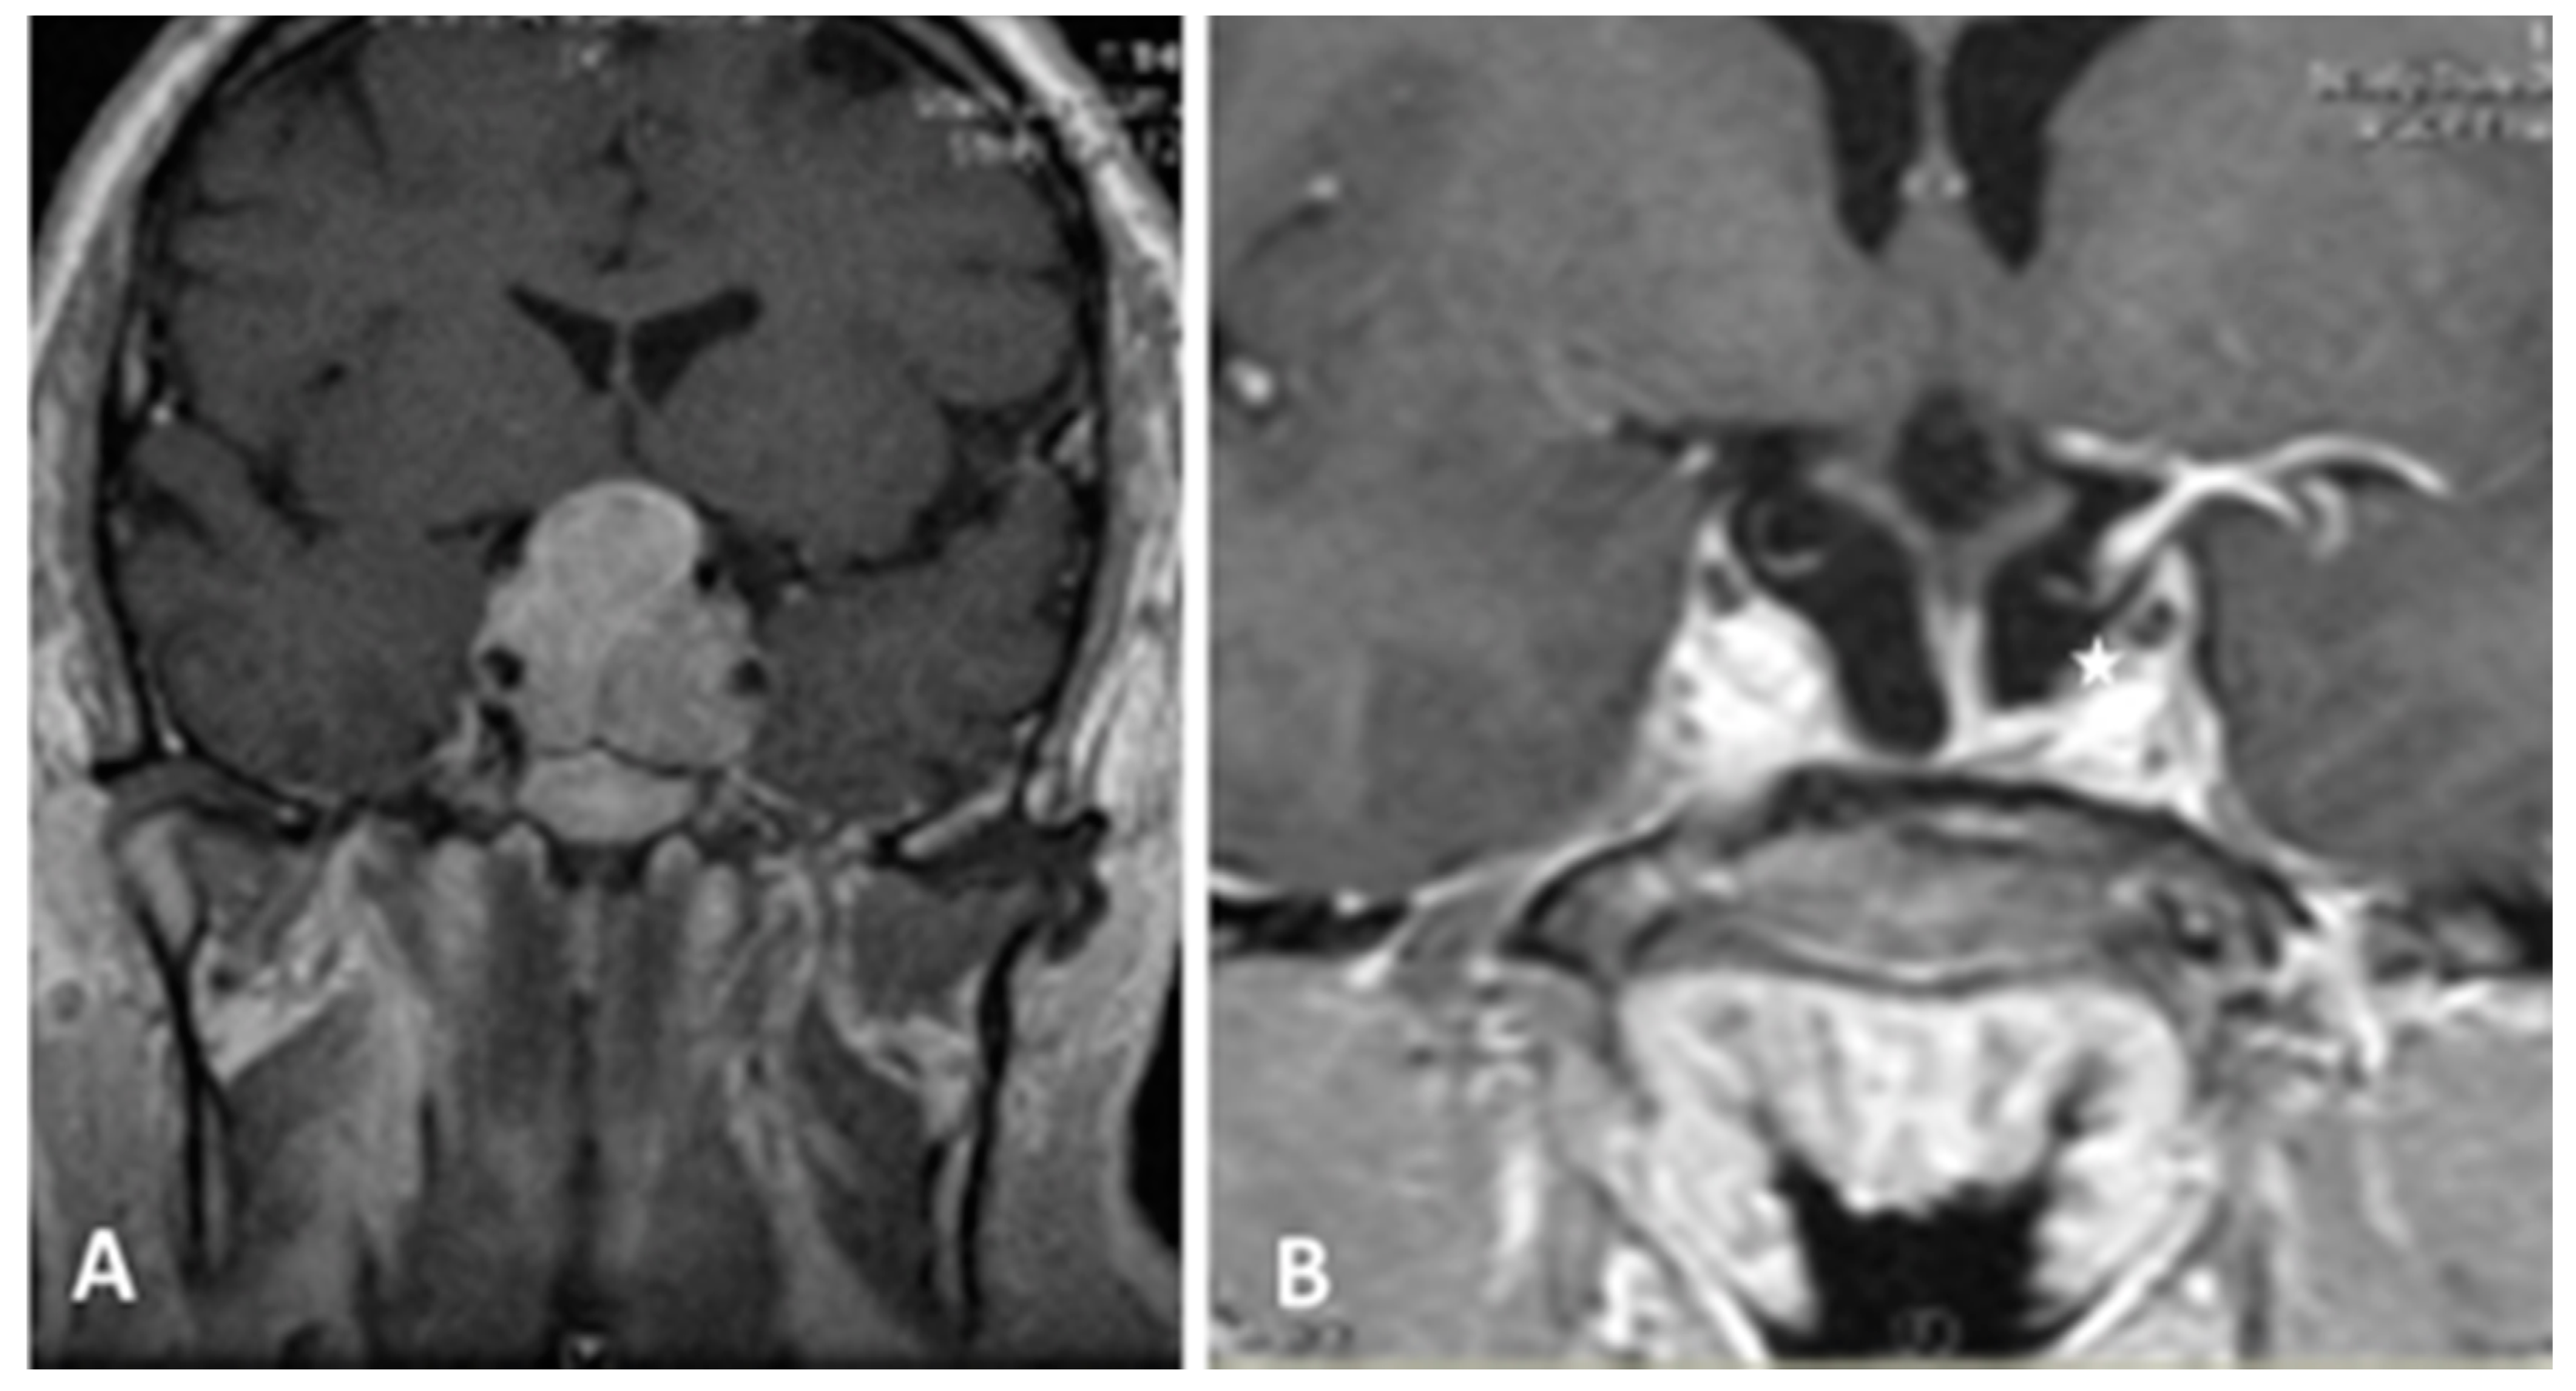

- Chibbaro, S.; Ganau, M.; Gubian, A.; Scibilia, A.; Todeschi, J.; Riehm, S.; Moliere, S.; DeBry, C.; Goichot, B.; Proust, F.; et al. The Role of Endoscopic Endonasal Approach in the Multimodal Management of Giant Pituitary Adenoma: Case Report and Literature Review. Asian J. Neurosurg. 2018, 13, 888–892. [Google Scholar]